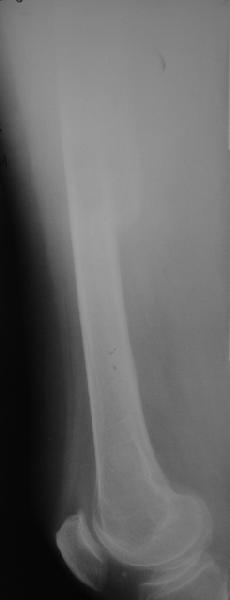

На прошлой неделе пациентке 74 лет, было выполнено цементное эндопротезирование тазобедренного сустава по поводу перелома шейки бедра.Активизирована на следующий день, ходила с костылями, нагрузка полная.Дело близилось к выписке, когда она, подскользнувшись упала в палате и получила то, что  видите на снимках.Что бы Вы стали делать в подобной ситуации? Заранее спасибо.